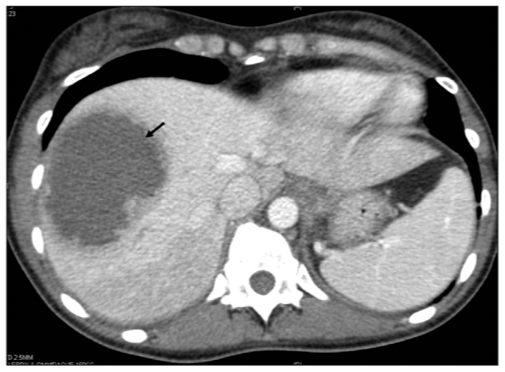

CT scan abdomen showing pyogenic abscess in the right lobe of the liver

imaging: chest x-ray will show elevation of diaphragm and basal lung lobe collapse. ultrasound and CT scan is used to define the abscess.